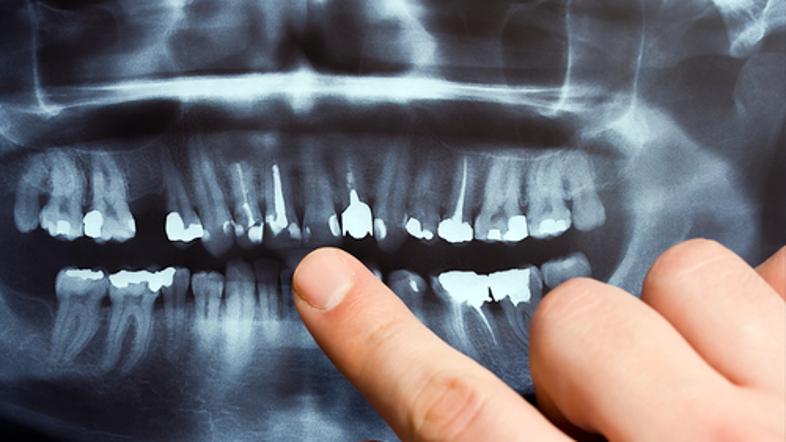

Rentgensko slikanje zob Shutterstock

Zaradi rentgenskega slikanja zob imate lahko dvakrat več možnosti, da zbolite za rakom na možganih, ugotavlja najnovejša študija. Znanstveniki kljub temu opozarjajo, da zaradi tega panika ni potrebna.